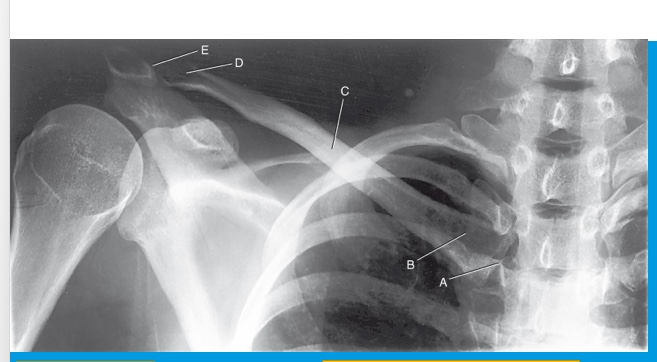

A

sternal extremity

B

body

C

acromial extremity

D

AC joint

E